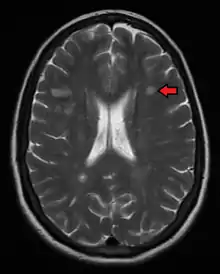

The name multiple sclerosis refers to the scars (sclerae – better known as plaques or lesions) that form in the nervous system. These lesions most commonly affect the white matter in the optic nerve, brain stem, basal ganglia, and spinal cord, or white matter tracts close to the lateral ventricles.[1] The function of white matter cells is to carry signals between grey matter areas, where the processing is done, and the rest of the body. The peripheral nervous system is rarely involved.[8]

To be specific, MS involves the loss of oligodendrocytes, the cells responsible for creating and maintaining a fatty layer—known as the myelin sheath—which helps the neurons carry electrical signals (action potentials).[1] This results in a thinning or complete loss of myelin, and as the disease advances, the breakdown of the axons of neurons. When the myelin is lost, a neuron can no longer effectively conduct electrical signals.[8] A repair process, called remyelination, takes place in early phases of the disease, but the oligodendrocytes are unable to completely rebuild the cell's myelin sheath.[61] Repeated attacks lead to successively less effective remyelinations, until a scar-like plaque is built up around the damaged axons.[61] These scars are the origin of the symptoms and during an attack magnetic resonance imaging (MRI) often shows more than 10 new plaques.[1] This could indicate that some number of lesions exist, below which the brain is capable of repairing itself without producing noticeable consequences.[1] Another process involved in the creation of lesions is an abnormal increase in the number of astrocytes due to the destruction of nearby neurons.[1] A number of lesion patterns have been described.[62]

Magnetic resonance imaging (MRI) of the brain and spine may show areas of demyelination (lesions or plaques). Gadolinium can be administered intravenously as a contrast agent to highlight active plaques, and by elimination, demonstrate the existence of historical lesions not associated with symptoms at the moment of the evaluation.[69][70]